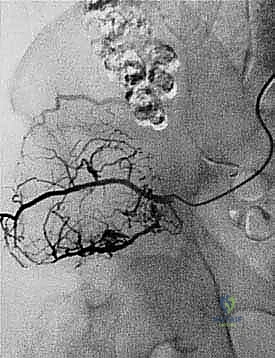

* Angiography: Mandatory. We need to map the vascular anatomy, which is often severely distorted by large pelvic tumors. This helps us determine the exact level of the aortic and common iliac bifurcations preoperatively and rule out direct vascular involvement. For vascular tumors like renal cell carcinoma metastases, preoperative embolization is always required to minimize intraoperative blood loss.

- Warning: The levels of these bifurcations can vary, especially with large tumor masses. Preoperative angiography is mandatory to avoid ligating the wrong vessels, particularly with midline tumors.

* Common Iliac Artery and Bifurcation: "Trace the common iliac artery distally. Remember our preoperative angiography? We confirmed the aortic bifurcation at L4 and the common iliac bifurcation at S1, the ala sacralis. It's crucial to identify both levels. Here, the common iliac artery divides into the external and internal iliac arteries."